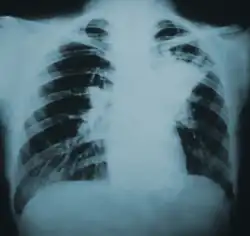

| Lung infiltration in blastomycosis. | |

Blastomycosis, also known as Gilchrist's disease, is a fungal infection, typically of the lungs, which can spread to brain, stomach, intestine and skin, where it appears as crusting purplish warty plaques with a roundish bumpy edge and central depression.[2][7] Around half of the people with the disease have symptoms, which can include fever, cough, night sweats, muscle pains, weight loss, chest pain, and fatigue.[5] Symptoms usually develop between three weeks and three months after breathing in the spores.[5] In 25% to 40% of cases, the infection also spreads to other parts of the body, such as the skin, bones, or central nervous system.[8] Although blastomycosis is especially dangerous for those with weak immune systems, most people diagnosed with blastomycosis have healthy immune systems.[8]

Blastomycosis manifests as a primary lung infection in about 79% of cases.[8] The onset is relatively slow, and symptoms are suggestive of bacterial pneumonia, often leading to initial treatment with antibacterials. Because the symptoms are variable and nonspecific, blastomycosis is often not even considered in differential diagnosis until antibacterial treatment has failed, unless there are known risk factors or skin lesions.[8] The disease may be misdiagnosed as a carcinoma, leading in some cases to surgical removal of the affected tissue.[19] Upper lung lobes are involved somewhat more frequently than lower lobes.[20] If untreated, many cases progress over months to years to become disseminated blastomycosis.

Blastomycosis in the lungs may present a variety of symptoms, or no symptoms at all.[8] If symptoms are present they may range from mild pneumonia resembling a pneumococcal infection to acute respiratory distress syndrome (ARDS).[8] Common symptoms include fever, chills, headache, coughing, difficulty breathing, chest pain, and malaise.[8] Without treatment, cases may progress to chronic pneumonia or ARDS.[8]